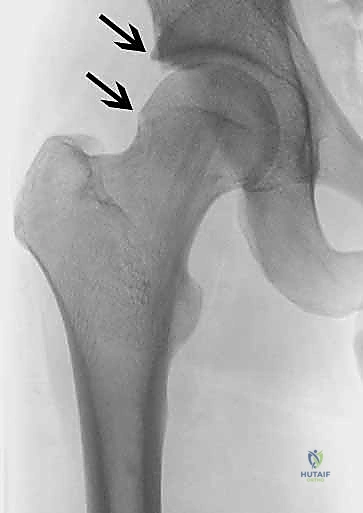

- الأشعة السينية (X-rays): لتقييم شكل العظام، قياس "زاوية ألفا" (Alpha Angle)، وتحديد وجود نتوءات الكامة أو الكماشة.

يحدث هذا النوع عندما لا يكون رأس عظم الفخذ كروياً بشكل مثالي. بدلاً من ذلك، تتكون نتوءات عظمية إضافية عند منطقة التقاء رأس وعنق الفخذ. هذا الشكل غير الدائري يجعله يحتك بقوة بحافة التجويف (الحُق) أثناء الحركة، مما يؤدي إلى "كشط" وتمزيق الغضروف والشفا الحقي. هذا النوع شائع جداً بين الشباب والرياضيين الذكور.

2. انحشار الكماشة (Pincer Impingement)

في هذا النوع، تكون المشكلة في التجويف (الحُق) نفسه. يمتد العظم البارز من الحُق ليغطي مساحة أكبر من الطبيعي من رأس عظم الفخذ. نتيجة لذلك، يتم "قرص" الشفا الحقي بين حافة التجويف وعنق عظم الفخذ عند ثني الورك. يُعد هذا النوع أكثر شيوعاً بين النساء في منتصف العمر.